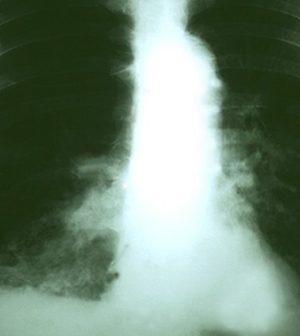

The Bacille Calmette-Guerin (BCG) vaccine is the only vaccine approved for preventing tuberculosis (TB) — a potentially fatal infectious disease that typically attacks the lungs. Because TB risk is low in the United States, the vaccine isn’t often given to American children, according to the U.S. Centers for Disease Control and Prevention.